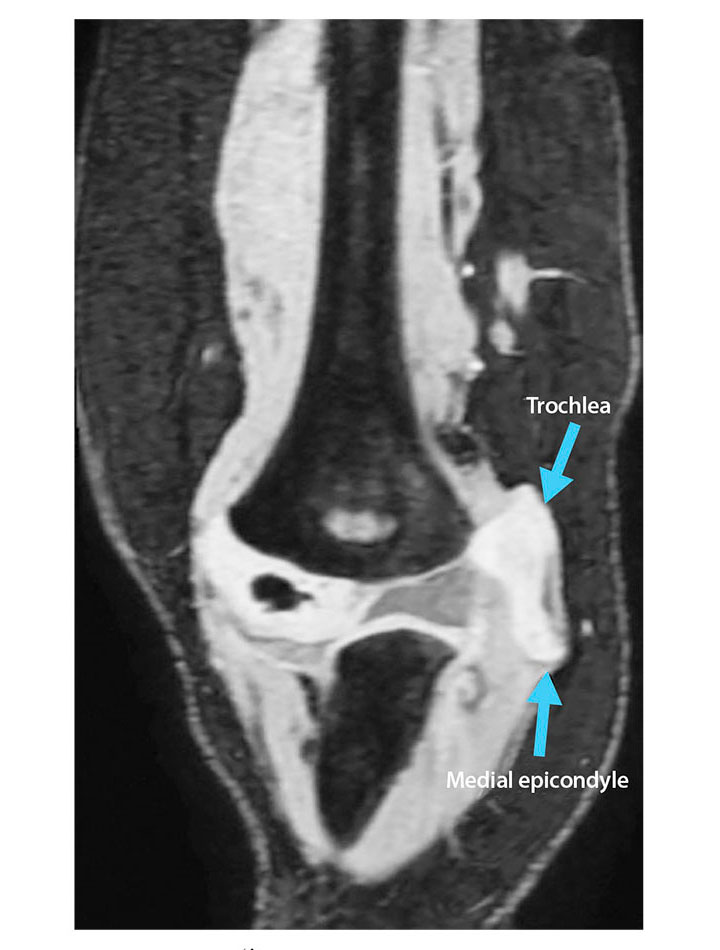

Fractures of the elbow are a common injury in children. Supracondylar humeral fractures are the most prevalent type of elbow fracture, whereas lateral condyle fractures are less common, and medial epicondyle are the least common.1 In children, medial epicondyle ossification occurs between ages 3 and 7 years.2 When a pediatric patient presents with elbow pain and decreased range of motion, a radiographic examination commonly is performed. However, because elbow fractures involving the unossified distal humerus might not be evident using this modality, other imaging examinations, such as magnetic resonance (MR) imaging, should be performed whenever a fracture is suspected. MR imaging can detect bone fractures as well as injury to surrounding anatomy such as cartilage, tendons, and ligaments. This case summary discusses a 2-year-old patient with a fracture of the distal humerus where the unossified cartilaginous trochlear and medial epicondyle fracture fragment was displaced from the joint. (see Figure 1).